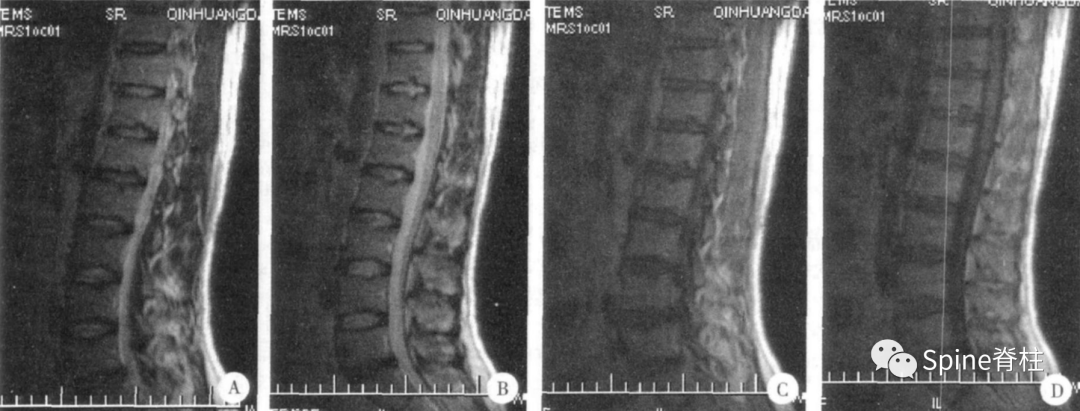

腰型休门氏病椎体终板不规则,T11-L4椎体中央Schmorl节,L2、L5椎体前缘Schmorl节,L2-L3椎间盘损伤(PMID: 24468666)。

腰型休门氏病。矢状位示腰1-2椎体轻微楔形变,冠状位示腰2椎体下缘及腰3椎体上下缘终板中央区略显凹陷;腰1椎体下缘,腰2-3椎体上下缘及腰 4 椎体上缘许莫氏结节;胸12-腰1椎体相邻缘终板中央偏后区不规则、略显内凹伴硬化。MRI上腰1-3椎体上缘许莫氏结节 (doi:10.3969/j.issn.1005-7234.2016.03.003)。

腰型休门氏病 (2008,MRI诊断腰椎休门氏病的临床意义)